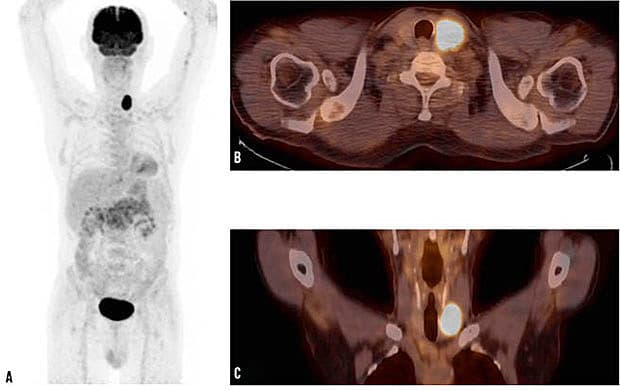

18F-FDG-PET/CT viser et thyroideaincidentalom hos en patient med thyroideacancer

En 67-årig mand, der tidligere var opereret for sigmoideumcancer, fik udført en 18F-FDG-PET/CT i den postoperative opfølgning. Helkrops-PET (A) samt aksial (B) og koronal (C) fusioneret PET/CT viste et incidentalom med kraftigt øget FDG-optagelse (maksimal standardiseret optagelsesværdi 15,26) i venstre thyroidealap. En thyroideascintigrafi (99mTc) viste et hypofungerende (»koldt«) område svarende til det FDG-positive incidentalom i venstre thyroidealap. En supplerende ultralydskanning viste en solid proces, hvorfra man udførte finnålsaspirationsbiopsi, som viste neoplasi. Patienten gennemgik total tyroidektomi, og diagnosen minimalt invasivt follikulært karcinom blev bekræftet. Postoperativt blev patienten ablateret med radiojod. Et år senere viste en helkrops-123I-skanning ingen tegn på restthyroideavæv. Desuden viste en 18F-FDG-PET/CT ingen tegn på recidiv af den tidligere sigmoideumcancer.